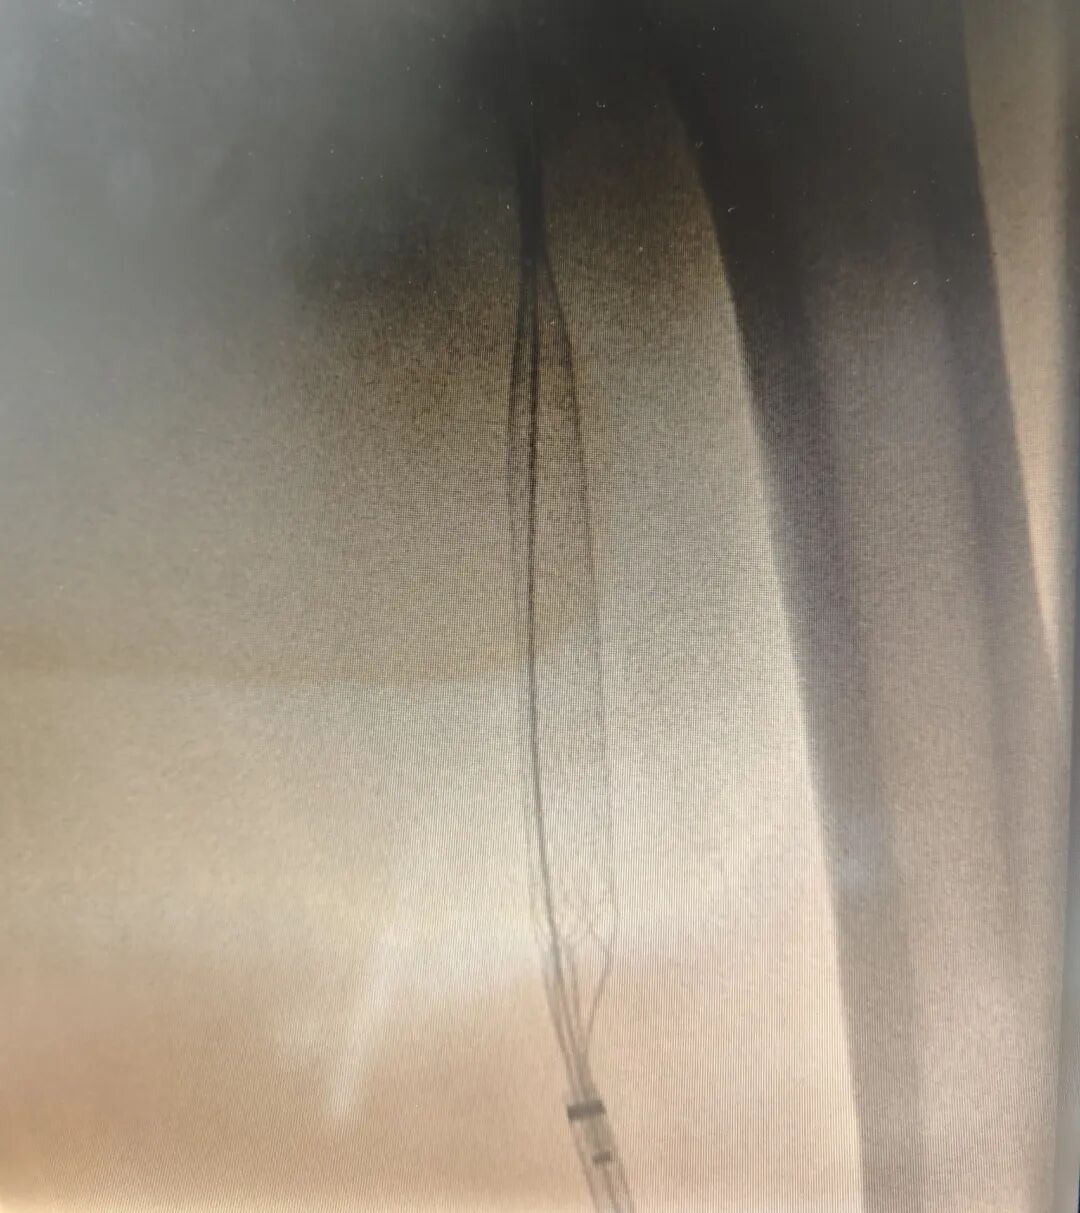

术中造影

田明主任精准操作,经鞘管将静脉取栓支架推送至髂总静脉,并一路延伸至股浅静脉,通过四次小心翼翼的反复拉栓,成功清除大量血栓。最终,复查造影传来捷报:患者股浅静脉、髂静脉及股静脉血流通畅,未见残余血栓,手术获得圆满成功!这一结果让手术室里的所有人都松了一口气,也意味着这场与病魔的激烈较量取得了阶段性的胜利。